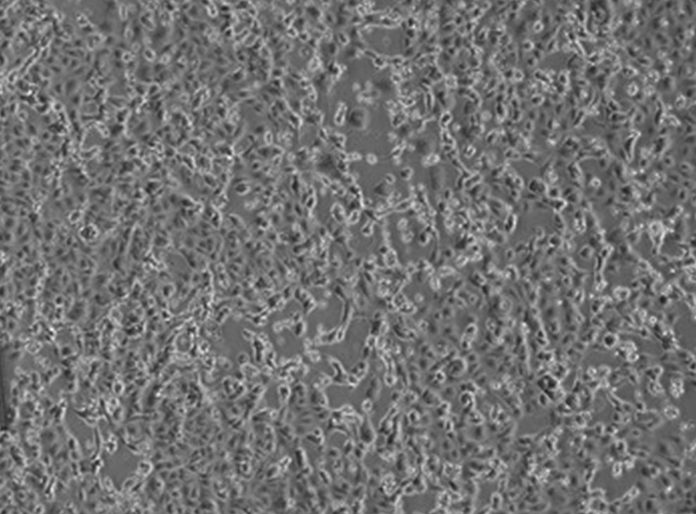

ROMA (ITALPRESS) – Notizie positive sul ricercatore italiano arrivato dalla Cecchignola, dopo il rimpatrio da Wuhan, risultato positivo al test del Coronavirus e ricoverato all’Istituto Spallanzani: “E’ in buone condizioni generali con quadro clinico invariato; persiste lieve febbricola e iperemia congiuntivale in fase di risoluzione. Il paziente ha iniziato terapia antivirale. Il giovane è assolutamente sereno, mantiene costanti contatti con la sua famiglia e con gli amici e continua il suo lavoro di recercatore”, si legge nel bollettino emesso dai medici questa mattina. “Il ministero della Salute ci ha comunicato che sta arrivando all’Istituto una signora a scopo precauzionale dalla Cecchignola. Ne verificheremo le condizioni”, comunicano i medici dell’Istituto Spallanzani parlando con i giornalisti.

Continuano a essere stazionarie le condizioni di salute della coppia di cittadini cinesi: “I due cittadini cinesi provenienti dalla città di Wuhan sono tuttora in terapia intensiva. Le loro condizioni cliniche permangono stabili, con parametri emodinamici invariati. Continua il trattamento antivirale con il farmaco remdesivir. La prognosi – conclude il bollettino è tuttora riservata”.